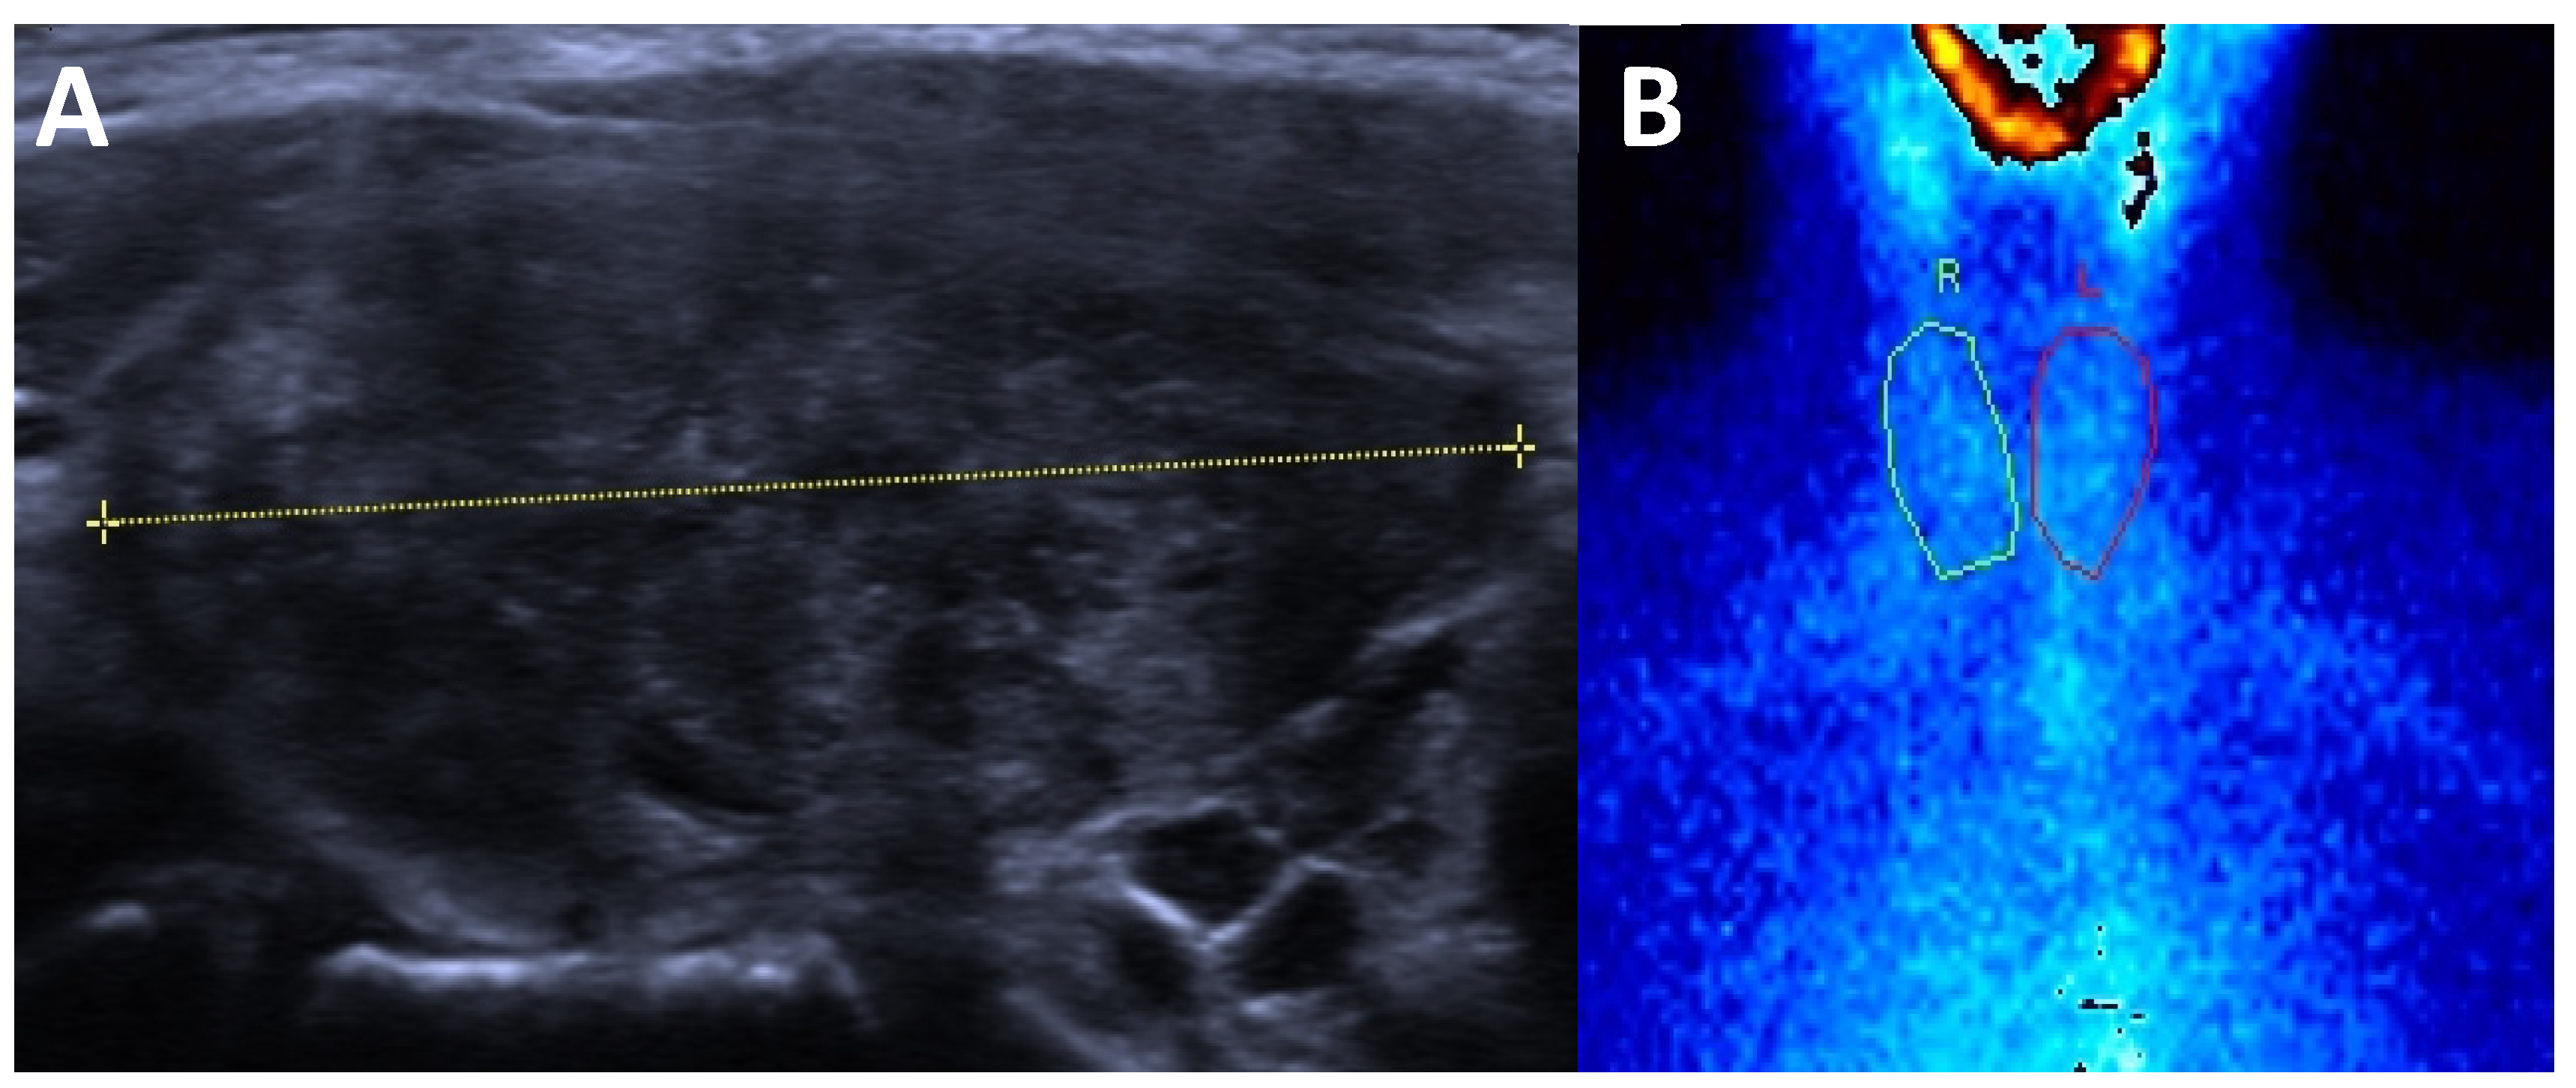

3. Thyroid Ultrasound in Thyroid Dysfunctions

3.1. Hyperthyroidism

3.2. Hypothyroidism